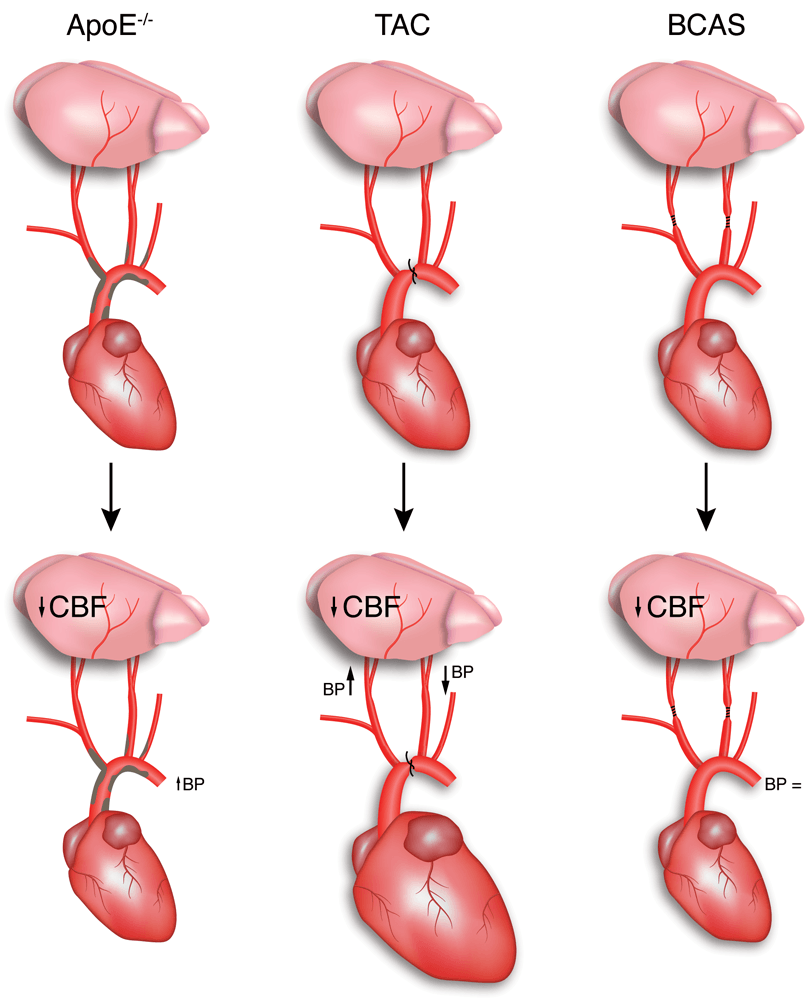

Chapter 2 Figure 1Most commonly used models for atherosclerosis, heart failure and hypoperfusion to study the effect of cardiovascular risk factors on the brain.